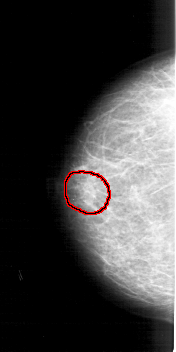

A_1982_1.LEFT_MLO

LEFT_MLO LINES 5296 PIXELS_PER_LINE 2596 BITS_PER_PIXEL 12 RESOLUTION 43.5 OVERLAY

FILE: A_1982_1.LEFT_MLO.OVERLAY

TOTAL_ABNORMALITIES 1

ABNORMALITY 1

LESION_TYPE MASS SHAPE OVAL MARGINS ILL_DEFINED

ASSESSMENT 4

SUBTLETY 3

PATHOLOGY BENIGN

TOTAL_OUTLINES 1

BOUNDARY